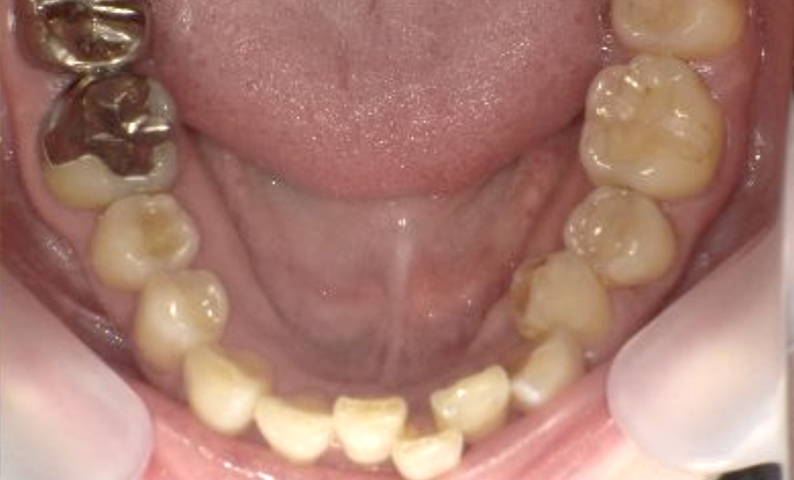

症例_003 下顎だけの部分矯正

治療期間:10ヶ月金額:24万円+税女性前歯のガタガタ下の前歯だけ上顎は補綴治療中